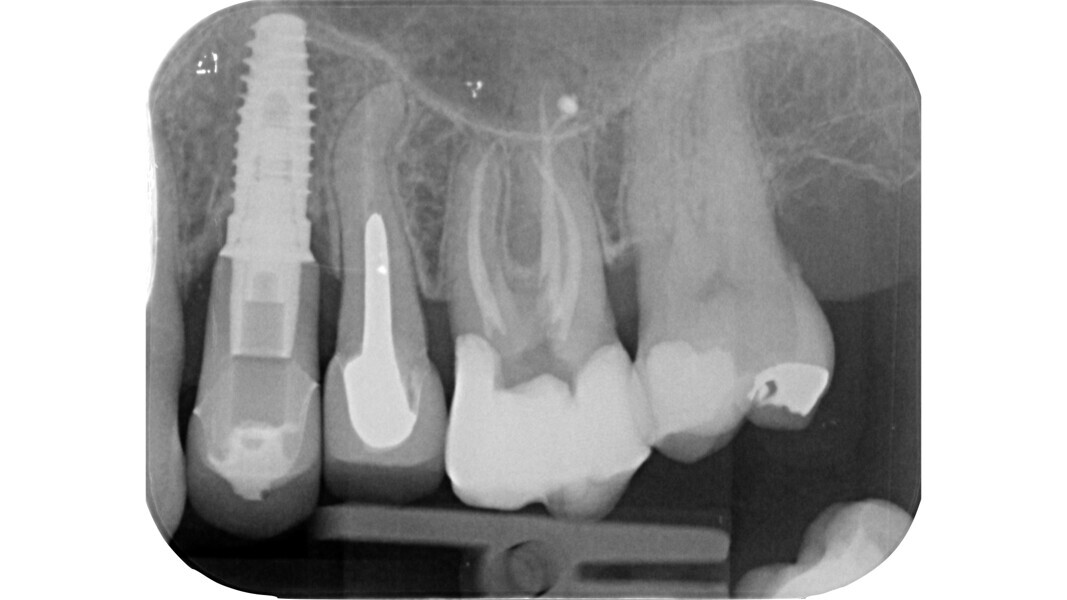

Fig. 1: Pre-op radiograph of a maxillary molar undergoing emergency treatment at another practice.

An inadequate access cavity in terms of position, depth and extension can lead to complications in the subsequent phases, making it impossible to locate the canal orifices, overstressing the mechanical nickel–titanium (NiTi) files or weakening the residual dental structure (Figs. 1–5). While, in the past, there was a tendency to emphasise the importance of a large access cavity that would allow the insertion of manual and mechanical instruments following the main axis of the canal, in recent years, the proposal of minimal access cavities defined in various ways (“ultra-conservative cavity”, “ninja cavity”, “truss access cavity”)4 has become predominant.

Fig. 2: Image of the access cavity prepared, showing excess removal of healthy tissue in the mesiobuccal and apical direction.